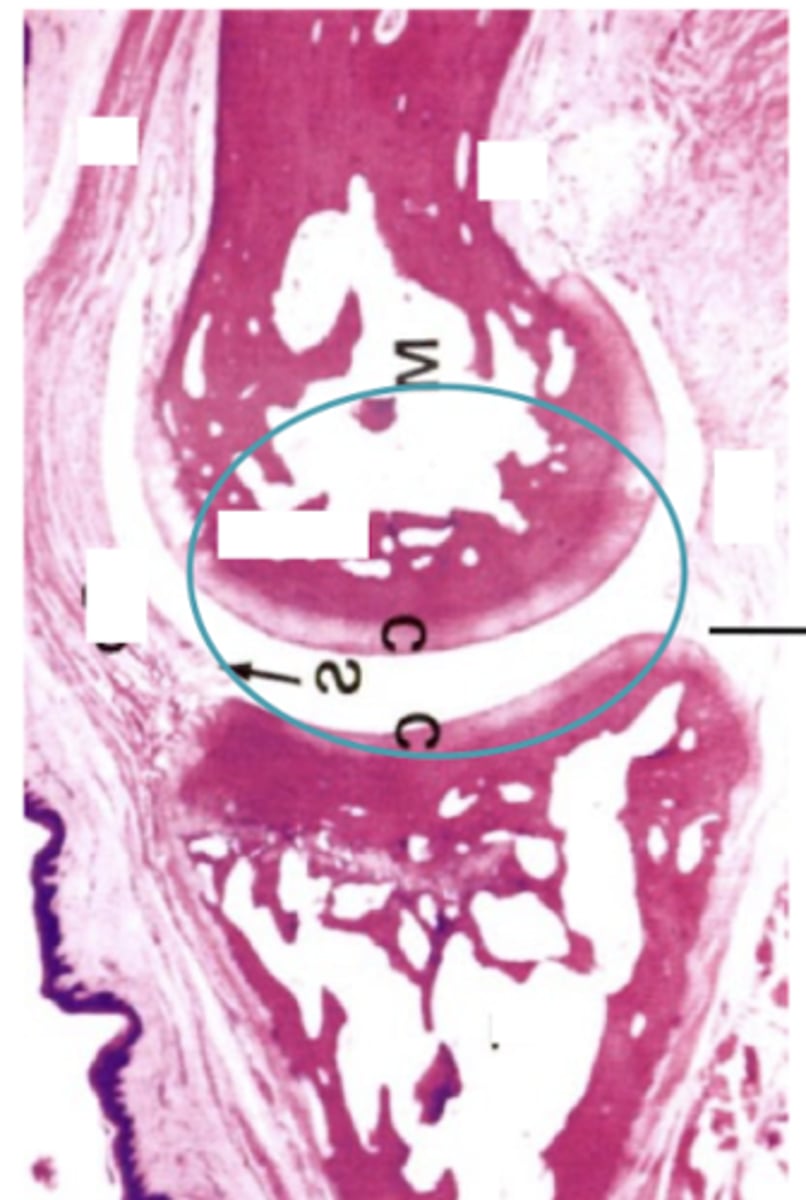

hyaline cartilage

what type of cartilage is located at all articular joint surfaces?

10

New cards

what type of cartilage is located in the respiratory system?

11

What does the NP stand for?

<p>What does the NP stand for?</p>

Anulus fibrosus

What does the AF stand for?

What type of joint is shown?

<p>What type of joint is shown?</p>

Articular cartilage (no perichondrium)

What type of cartilage is shown?

<p>What type of cartilage is shown?</p>